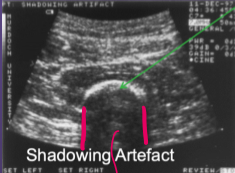

a. Name the type of artifact that is shown below?

b. What caused this artefact?

a. Shadowing artfect

b. Barrier soft tissue and bone